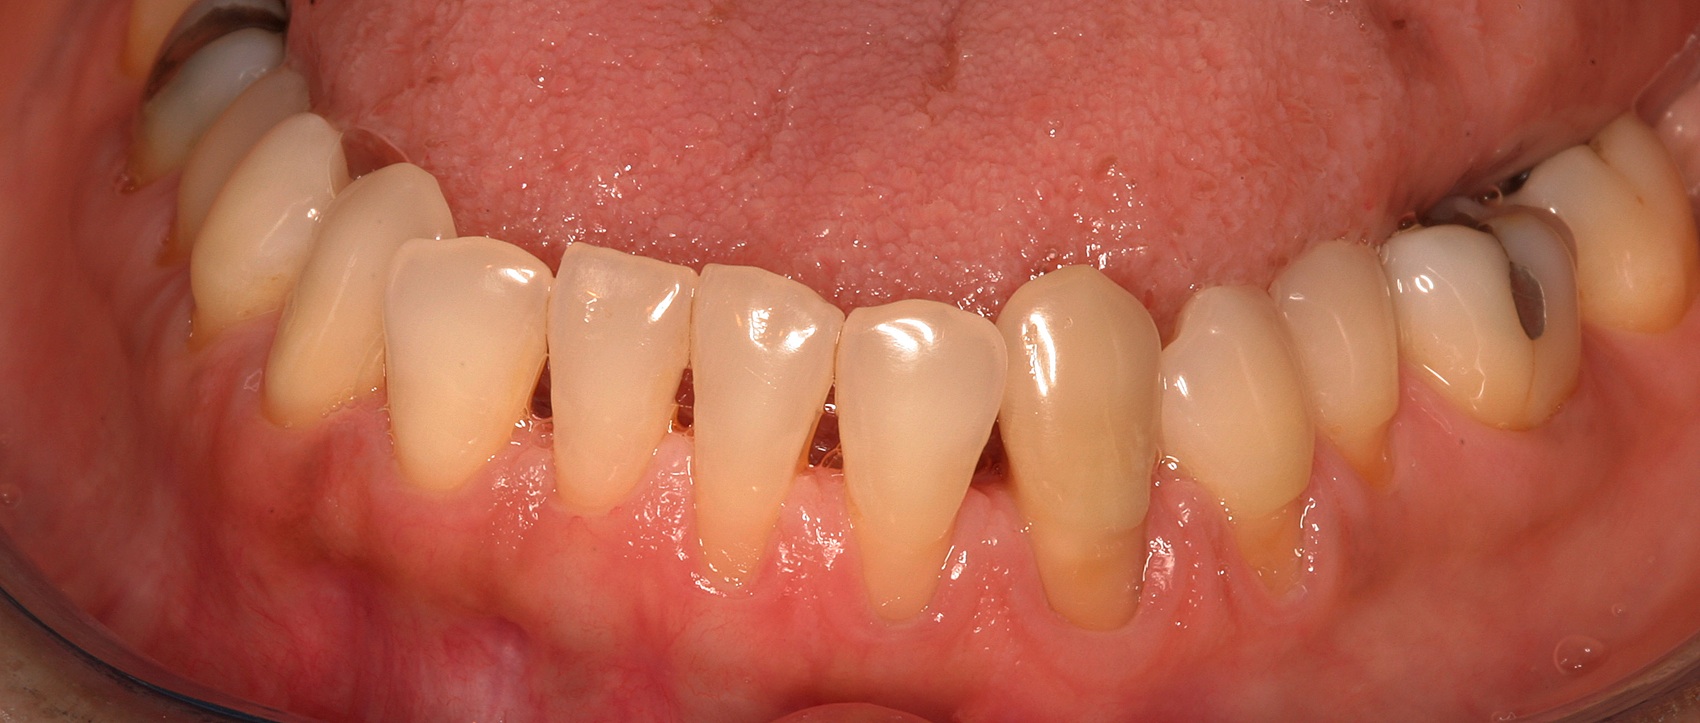

Preoperative recession.

Fig. 8

In the coming decades, restorative treatment for aging patients who experience facial growth with recession and erosion below the cemento-enamel junction because of tooth movement may be especially challenging. However, if dentists can employ the tenets of regeneration using autogenous tissues or a cellular dermal matrix combined with enamel matrix derivatives as a regulatory protein, they may predictably achieve large amounts of root coverage with thickened periodontium. This would not eliminate the need for restorative dentistry, but would enable restorative dentists to place restorations that are supragingival and are easily accessible for the patient and the therapist during maintenance (Figure 8 through Figure 10).